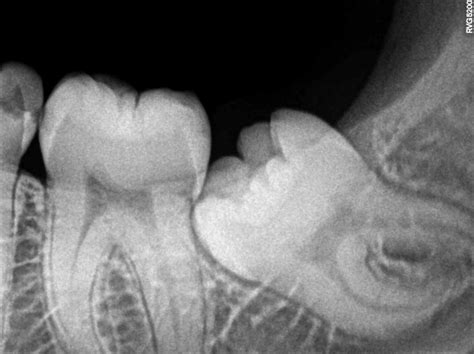

When these teeth begin to develop, they form at the very back of the dental arch. Because they are the last to erupt, they often encounter a space crunch. If there is insufficient room, the teeth become impacted. An impacted tooth is one that is unable to break through the gum line or emerge fully because it is blocked by adjacent teeth, soft tissue, or bone. This is a primary reason why dental professionals often recommend monitoring their growth via routine X-rays long before they cause symptomatic pain.

Dentists use advanced imaging to monitor the position and health of your 3rd molar teeth. During a routine exam, a panoramic X-ray is typically taken. This image provides a complete view of the upper and lower jaws, allowing the dentist to observe the angle of the teeth, their proximity to nerves, and whether they are likely to interfere with the alignment of your existing healthy teeth.

Partial Bony Impaction Part of the tooth is erupted; part is inside the jawbone. Extraction to prevent infection.